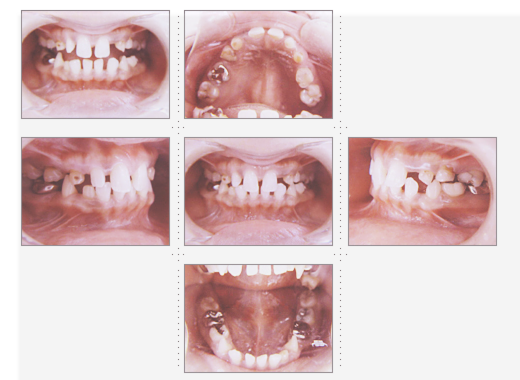

症例1

理学療法士 36才 女性

上下の歯並びを直したいというご希望で、来院。

術前と術後では、歯並び表情が変わった事はもちろんのこと、顔の形も変わり、「美容整形をしたように小顔になれました」と喜んでいただけました。